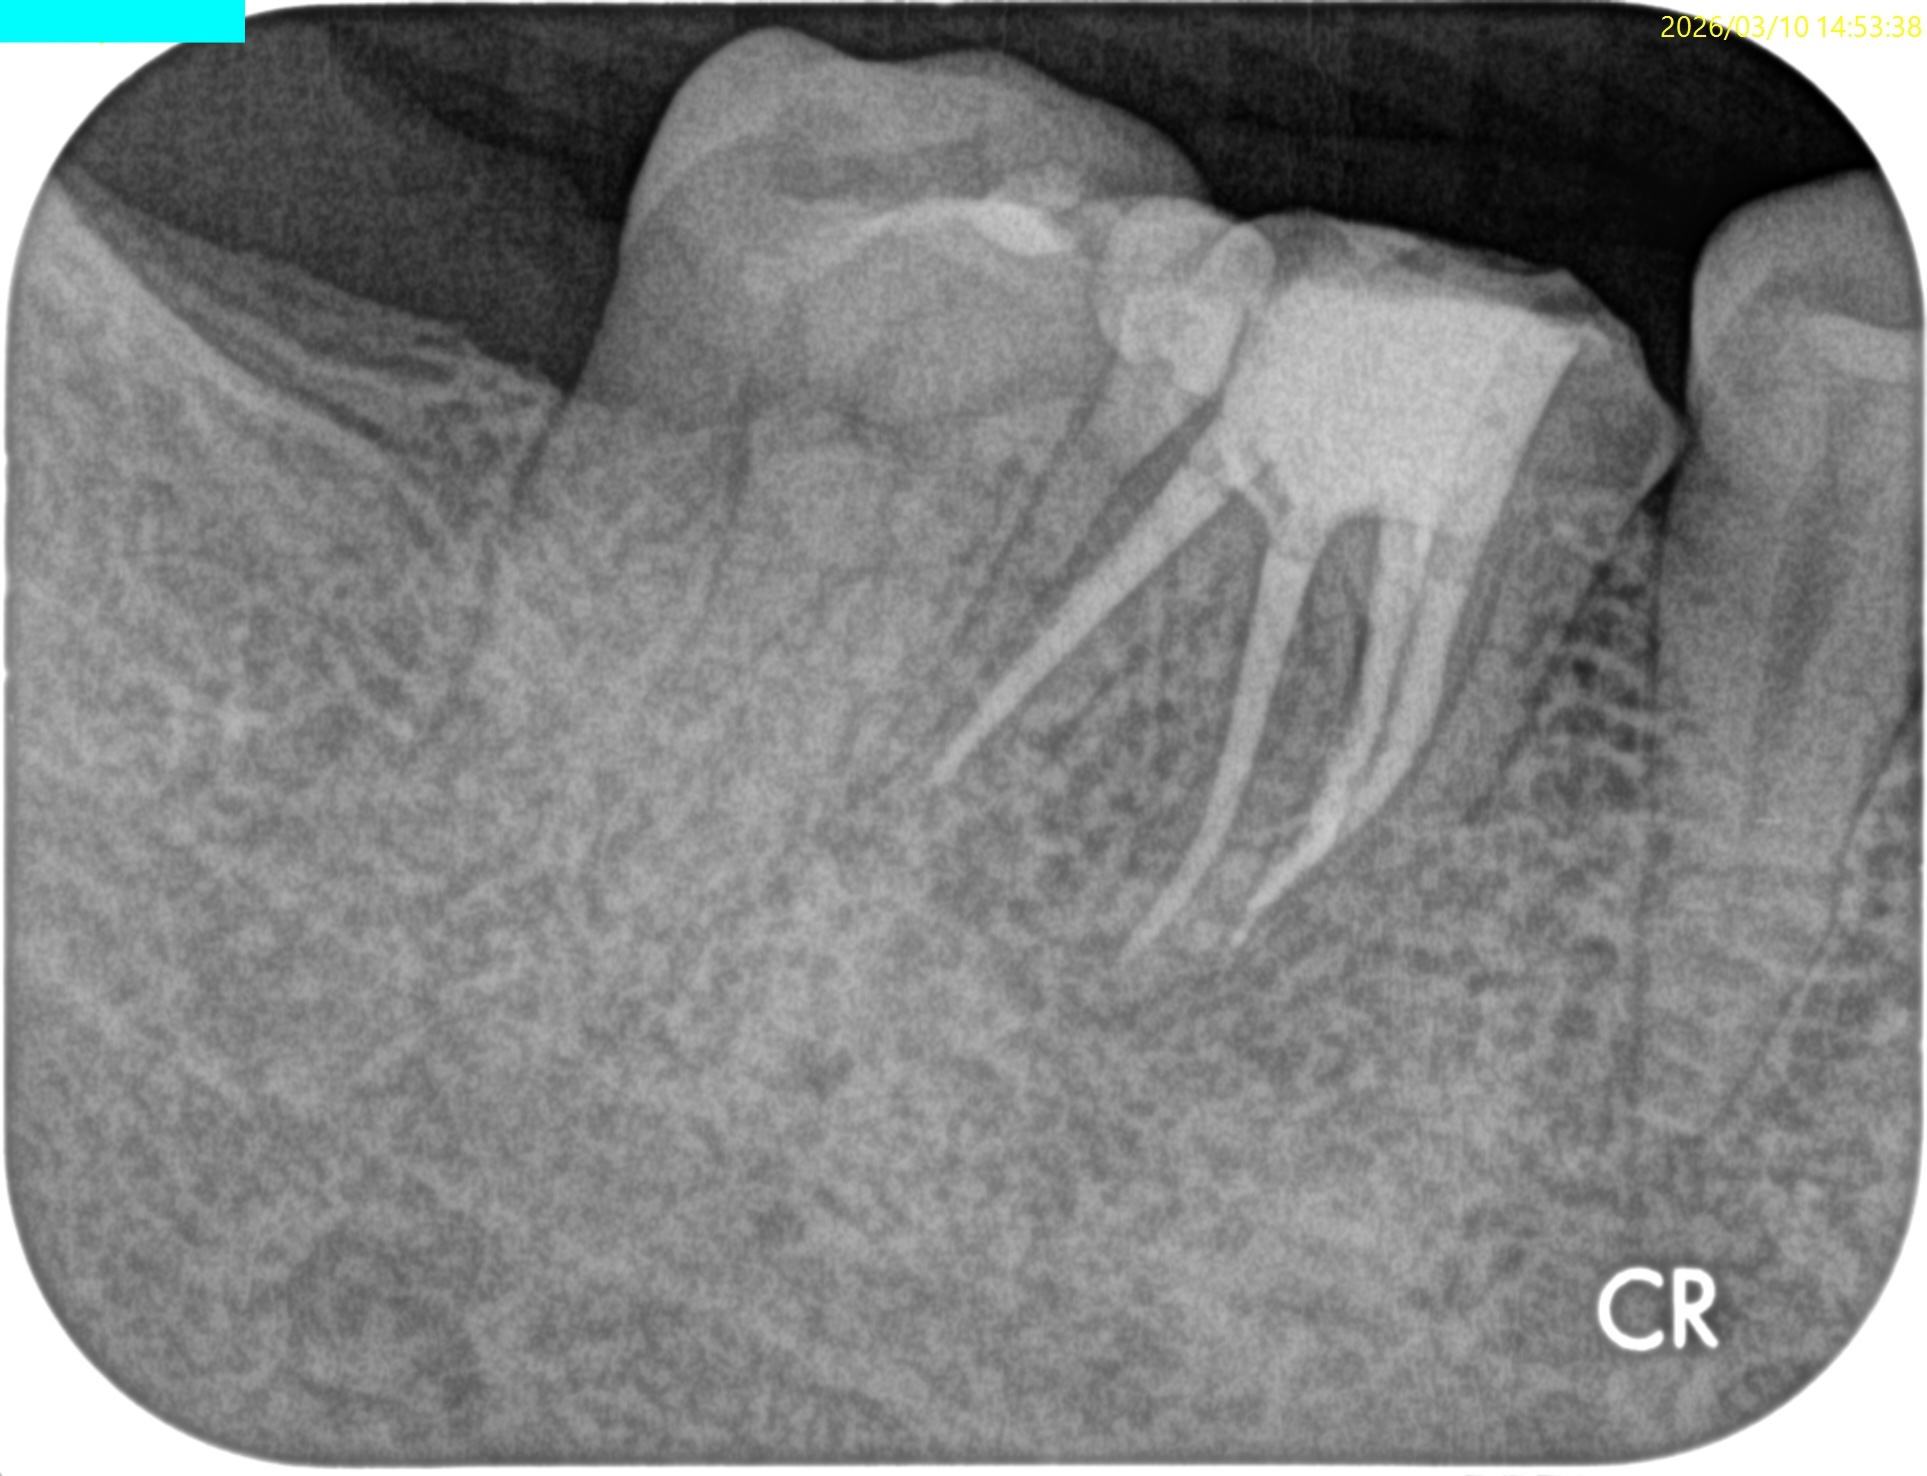

Pre-op Endo test(2025.2.14)

MB

ML

D

Radix

そこそこ湾曲度合いが強いRadix Entomolarisを有する#30だ。

が、D以外の根管はほぼ適切な根管治療がなされていない。

Radixにおいては未着手だ。